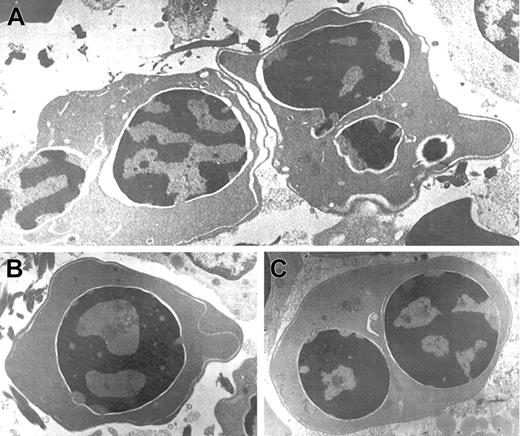

Optical microscopy morphology of peripheral and bone marrow hematopoiesis.

Binucleate erythroblast in peripheral blood (A). Erythroid hyperplasia with marked abnormalities (binucleate, trinucleate, and multinucleate late erythroblasts) (B,C,D). Abnormal erythroblasts showing anomalous distribution of chromatin (C,D), binucleate erythroblasts, and isolated trinuclear, tetranuclear (B), and aberrant multinuclear erythroblasts (B,D). May-Grünwald-Giemsa stain. Original magnifications: A and D, × 400; B, × 200; C, × 1000.

In this period, an extensive study ruled out red cell enzyme, membrane, hemoglobin, and thalassemic diseases. Tests for maternofetal isoimmunization were normal, and a bone marrow biopsy showed a normal osteogenesis with erythroid hyperplasia, excluding an aplastic red cell anemia. His red cells showed a normal agglutinability with anti-i antibody, and an acidified serum lysis test was negative (HEMPAS negative) in 3 samples and against 25 sera. At 3 months of life when the immunohematologic study was carried out, his hemoglobin was 67 g/L, mean corpuscular volume was 80 fL, platelets were 568 × 109/L, leucocytes were 10.2 × 109/L, including 10% of nucleated red cells, and reticulocytes were 0.5% (0.013 × 1012/L). Red cell morphology in peripheral blood showed scant binuclear erythroblasts (2%) (Figure 1).

At the age of 2 months a bone marrow examination showed erythroid hyperplasia and markedly abnormal erythropoiesis (Figure 1), including a substantial proportion of binuclear erythroblasts (20%) and a much smaller proportion of trinuclear, tetranuclear, and multinuclear erythroblasts (2%). Sideroblastic or megaloblastic anemias were ruled out. Granulocytopoiesis and megakariocytopoiesis were normal.